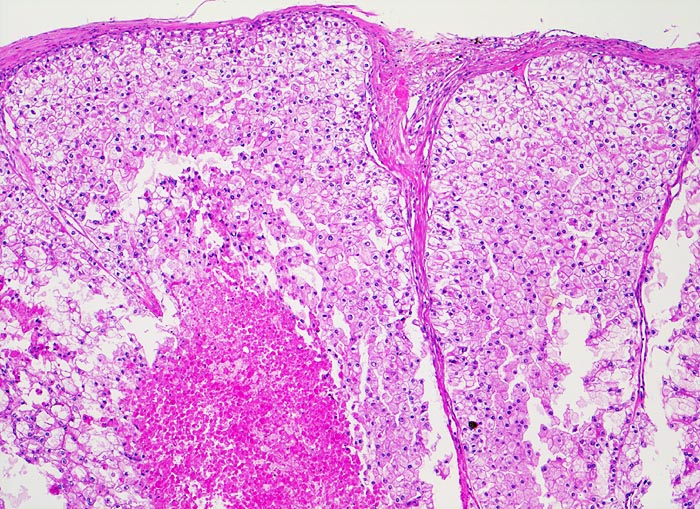

Basel 1MA/ Klarzelliges Nierenzellkarzinom

Klarzelliges Nierenzellkarzinom

Klarzellige (alte Bezeichnung: hellzellige) Nierenzellkarzinome sind mit einem Anteil von etwa 75% der häufigste Typ. Es ist charakterisiert durch Tumorezellen mit einem klaren und/oder eosinophilen Zytoplasma, bevorzugt solidem Wachstumsmuster und ausgeprägter Vaskularisation. Das helle Zytoplasma der Tumorzellen und der pflanzenzellartige Aspekt resultieren aus ihrem hohen Glykogen- und Neutralfettgehalt (> 22).

• Saum von komprimiertem und fibrosiertem Nierenparenchym unmittelbar angrenzend an das Karzinom (makroskopisch als Pseudokapsel imponierend). Übriges nicht-neoplastisches Restnierenparenchym mit leichter tubulointerstitieller Fibrose und Atrophie.

• Expansiv wachsender, scharf begrenzter knotiger Tumor ohne Durchbruch der Nierenkapsel.

• Wenig zellarmes Tumorstroma mit Blutungsresiduen.

• Solide Tumorzellaggregate eingefasst von dünnen Bindegewebssepten mit zahlreichen dünnwandigen Blutgefässen.

• Frische intratumorale Einblutungen und Blutungsresiduen (Siderinpigment)

• Polygonale Tumorzellen mit reichlich klarzelligem Zytoplasma und deutlichen Zellgrenzen.

• Hyperchromatische, polymorphe grosse Kerne mit prominenten Nukleolen (entspricht einem Grad 3 nach WHO/ISUP).